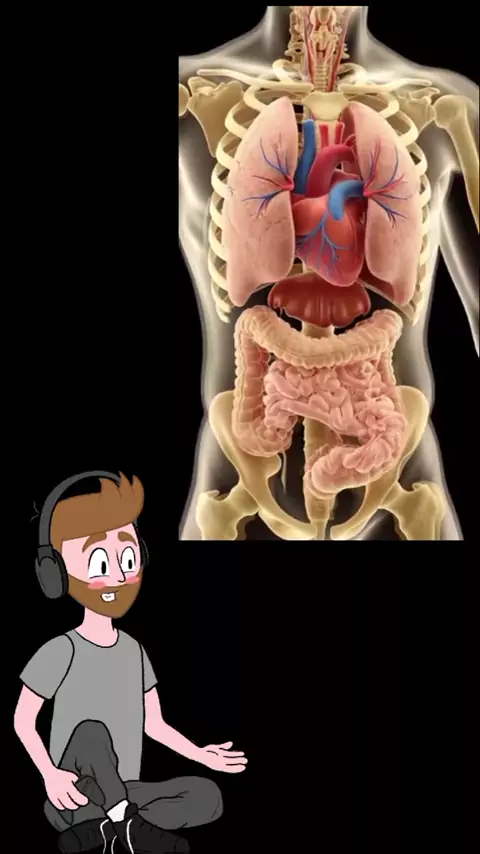

A musculatura do tronco é composta por vários grupos musculares importantes que dão suporte à coluna, protegem órgãos internos e permitem a mobilidade e estabilidade do corpo. Créditos: Prof. Jodonai Barbosa #músculos #anatomia #fisiologia #aula #medicina